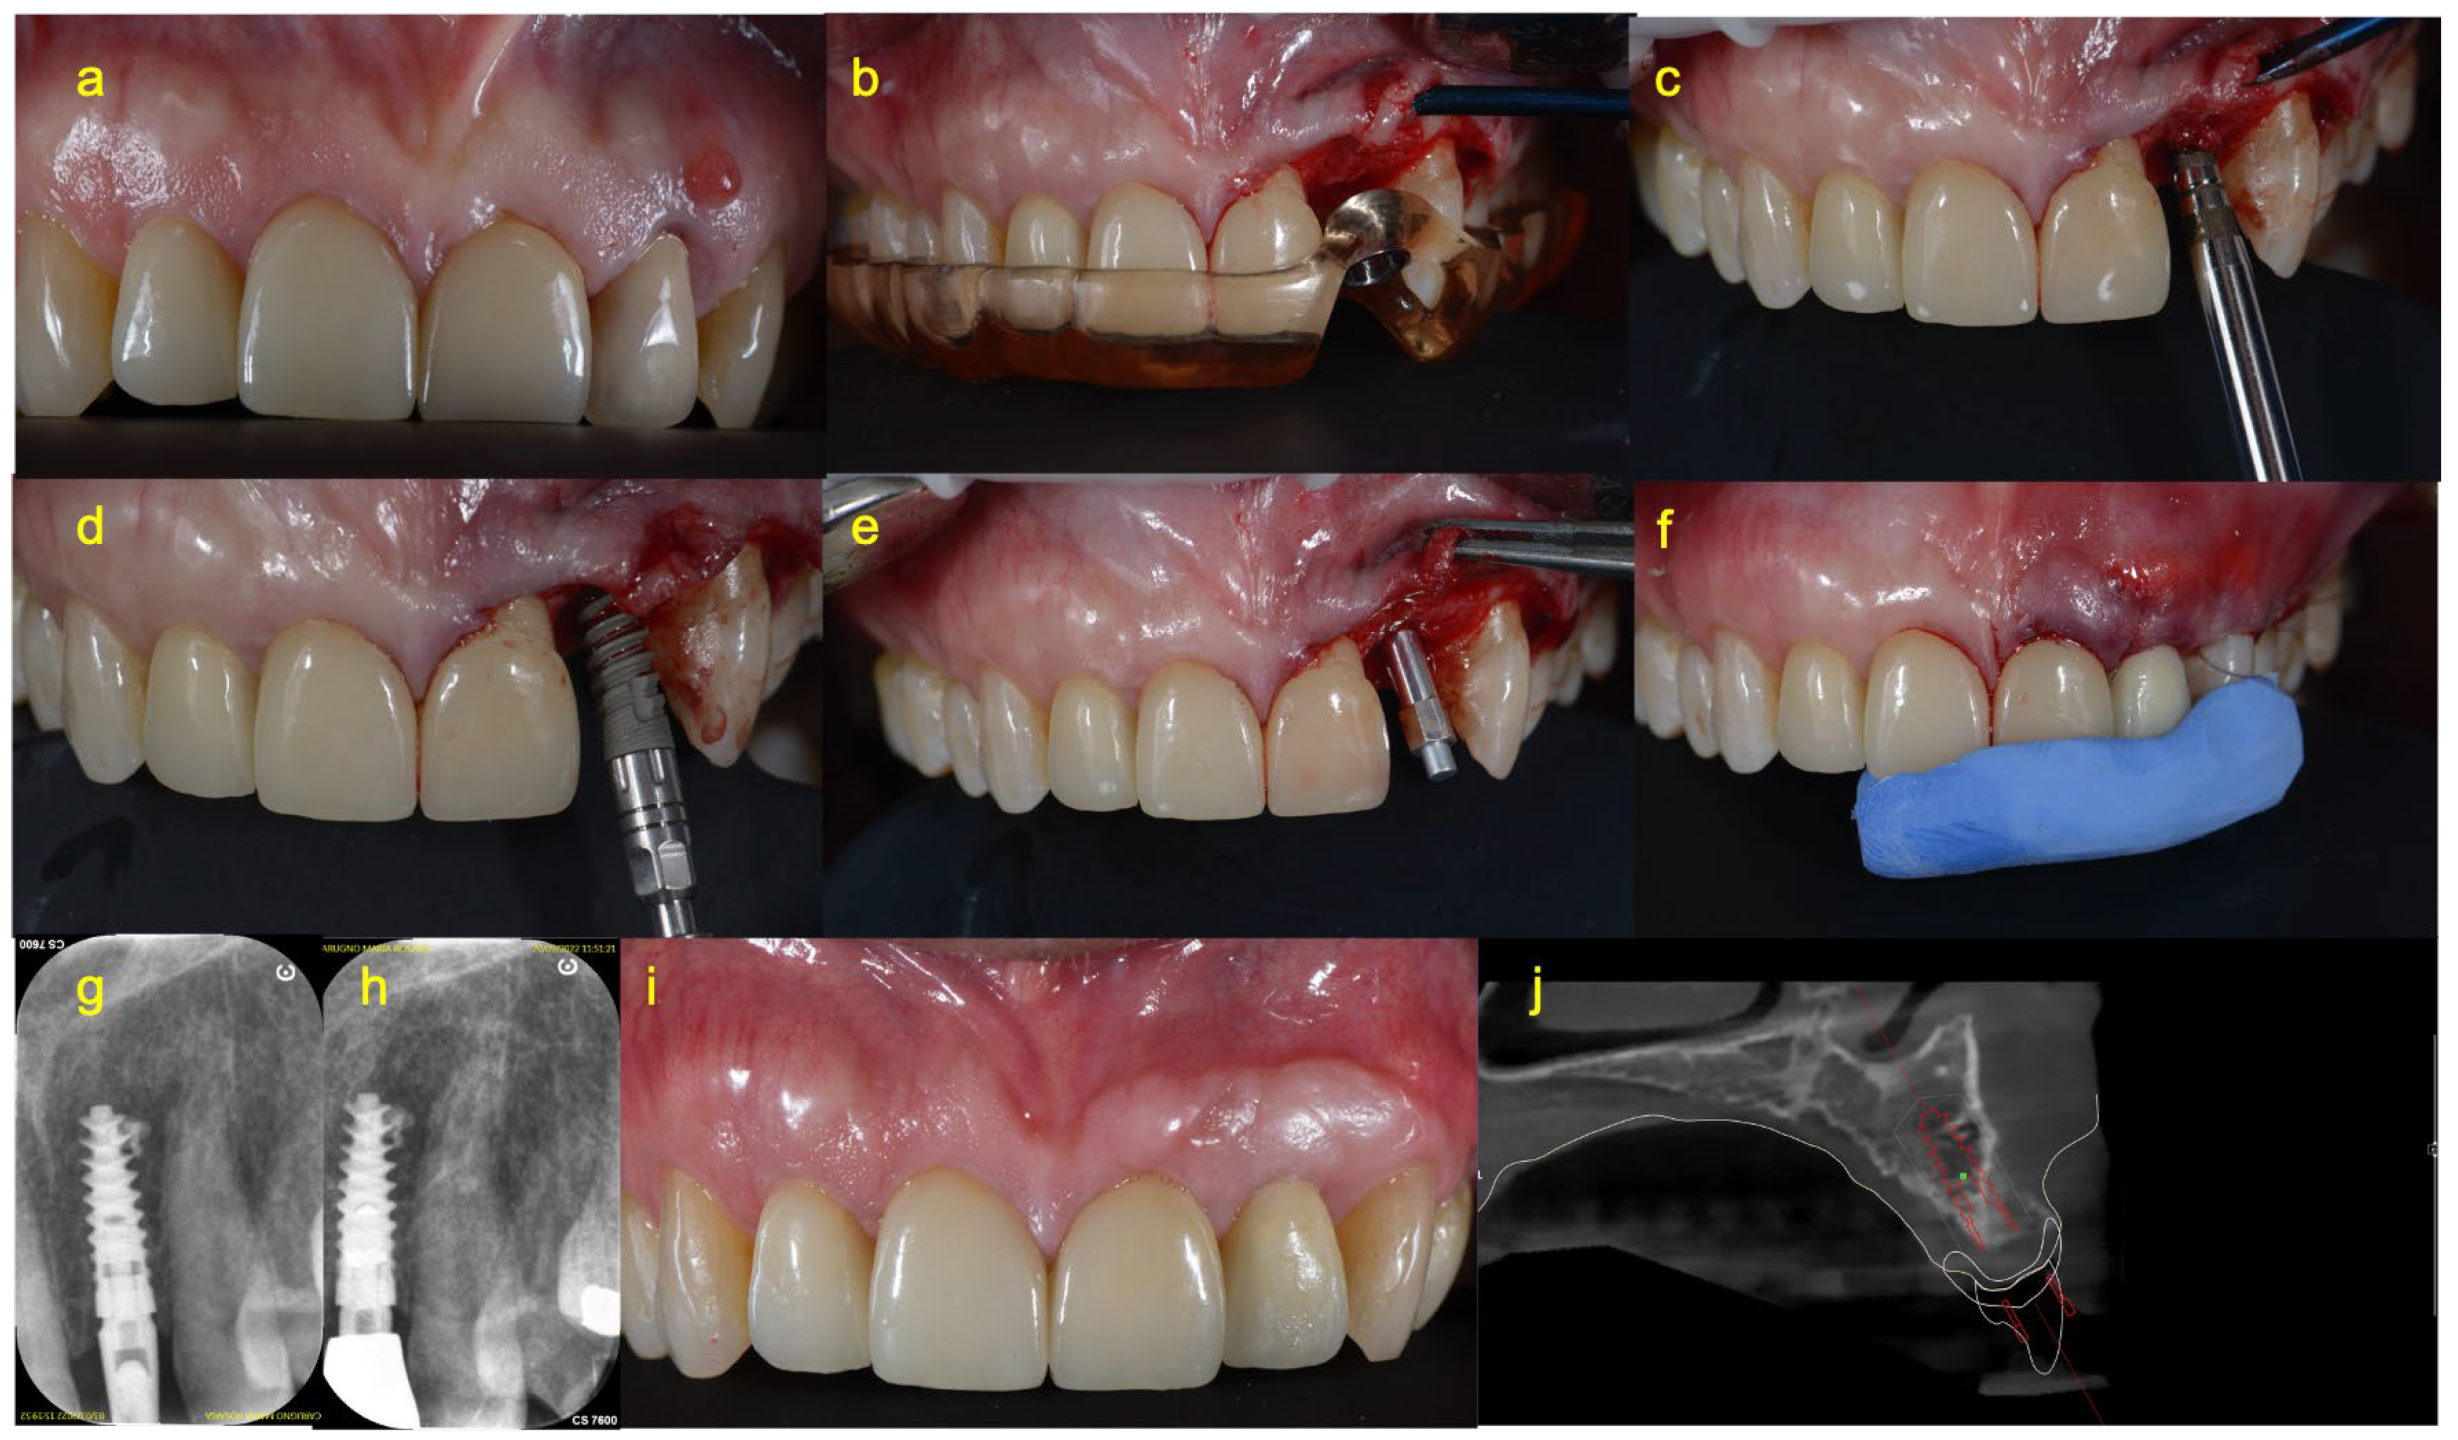

2.4. Surgical Procedure

2.5. Prosthetic Procedure of Immediate Loading Group (Group A)

2.6. Prosthetic Procedure of Delayed Loading Group (Group B)